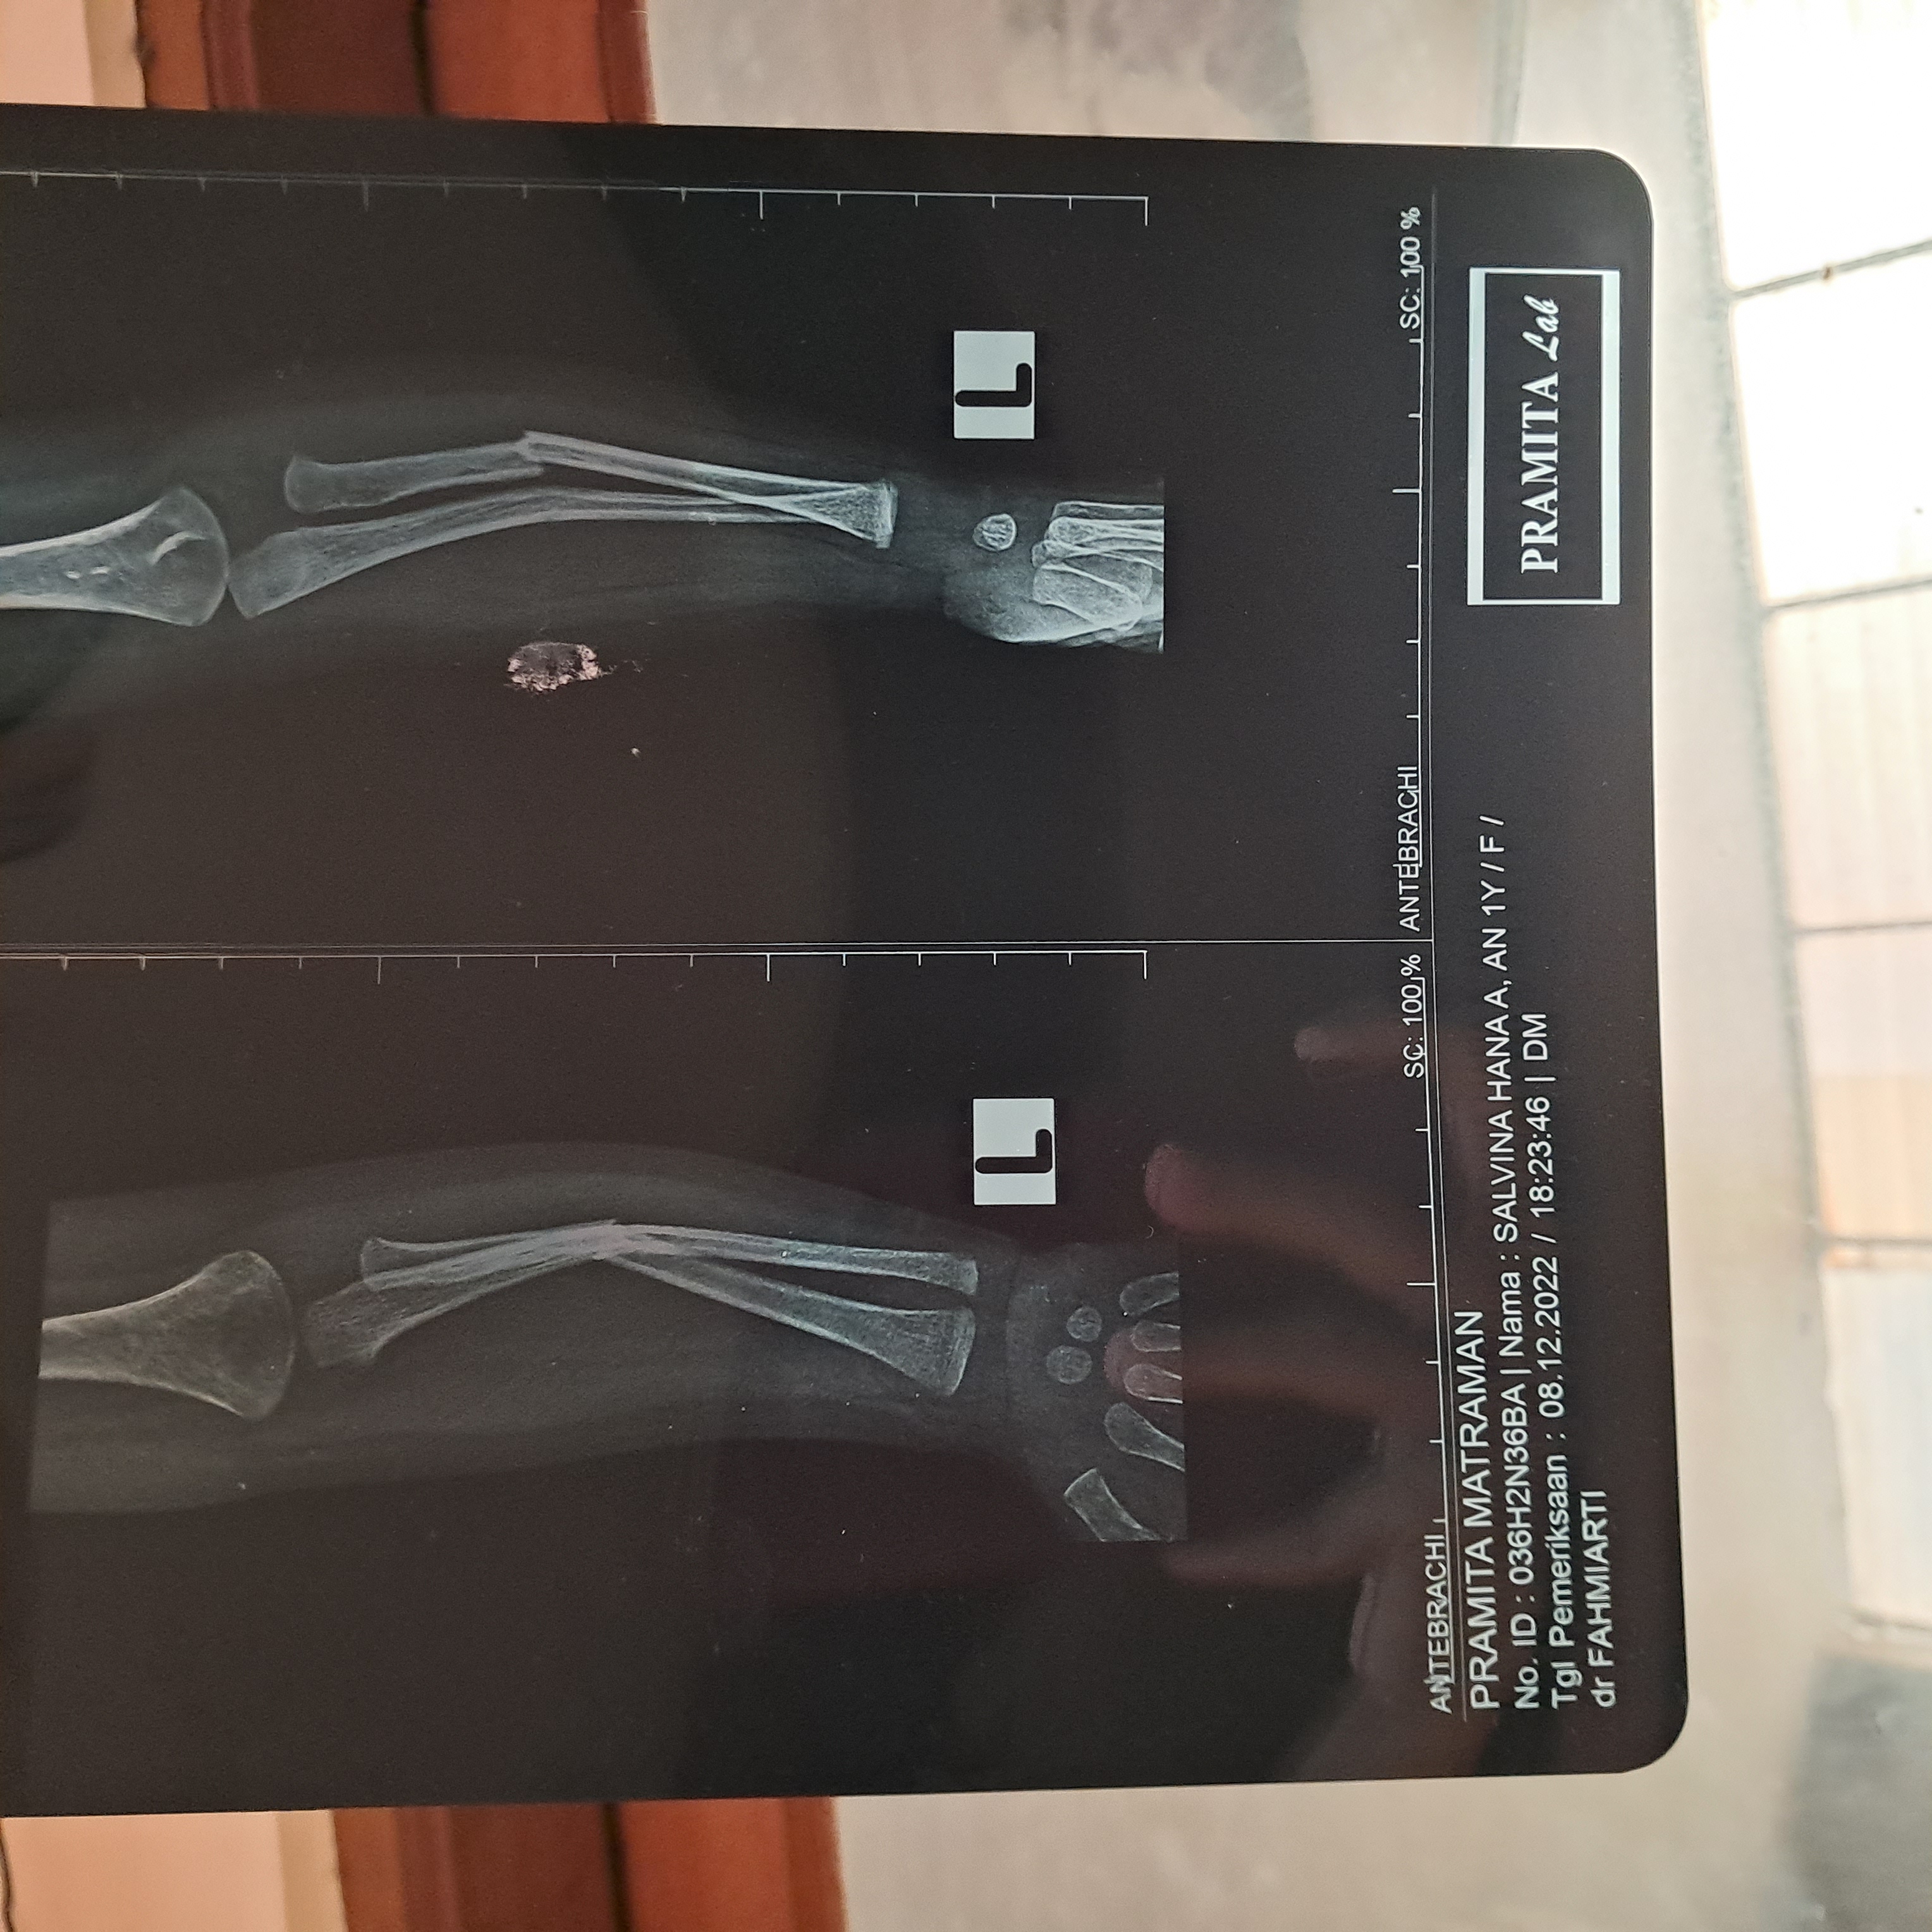

Untuk masalah tangan yang patah sudah di rontgen ulang dan hasilnya pun membaik.

Insya Allah awal tahun kontrol ke jantung dan ke dokter orthopedi, karena gipsnya belum dibuka.

Akhir bulan lalu, Salvina jatuh dari kasur. Posisinya tangan terlebih dahulu, jadi saat ini tangannya patah dan sedang dalam perawatan. Dan saat ini Aalvina lagi batuk pilek juga.